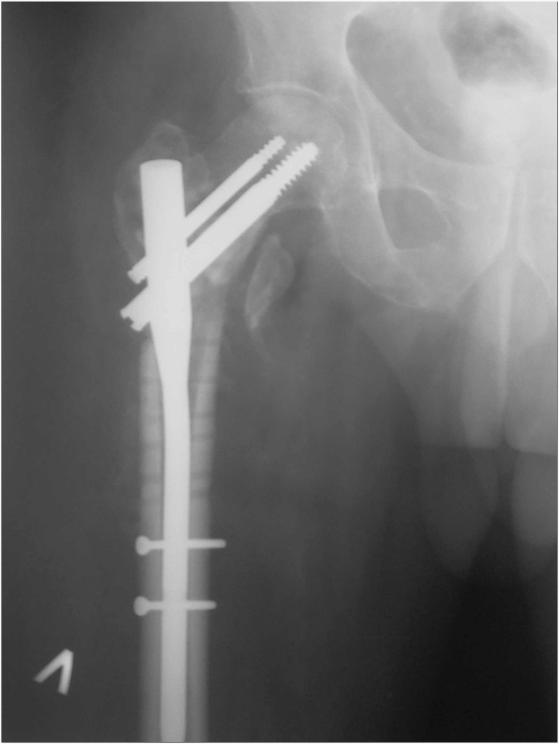

Поступил недавно из области 55-летний пациент с несращением проксимального отдела бедра (травма 4 мес. назад), после несостоятельного остеосинтеза 2 мес. назад - древняя угловая пластина, рядом спонгиозный винт через шейку бедра аж в вертлужную впадину. Внешне все тихо, аккуратный линейный рубец в вертельной области. Анализы спокойные. Во время удаления взял дважды посев (последнее время все удаления на всякий случай сеем) с интервалом минут в 20, с первого же винтика, потом из из ложа пластинки после удаления.Хотели тут же сделать реостеосинтез гамма стержнем, но укрочение и варус одномоментно устранить не удалось, поэтому оставили больного в дистракторе таз-бедро. На следующий день звонят микробиологи - в обоих посевах массивный рост клостридий. Назначили метрогил внутривенно. Через день как раз бумажка про первый посев подоспела - аж perfringens! Плюс еще какие-то стрептококки. Чувствительность есть, оба к амоксиклаву 4+, например. Cунул зонд до кости, взял оттуда посев - вроде ничего поначалу, но день на четвертый выросли опять те же клостридии. Вчера была неделя. Внешне рана спокойна. Температура нормальная. Остеосинтез если не делать - остается неопорная конечность. Так что делать надо. Растянуть аппаратом вроде удалось.Вопросы - как правильно выйти на операцию, и пройти далее? То есть ждать ли N-кратных стерильных посевов перед остеосинтезом? Если ждать, то N равно скольки? После операции - антибиотики? Как долго? Может, расшить зажившую рану после удаления, и положить туда спейсер из цемента с антибиотиками? Еще какие-то соображения-мысли-советы? Вообще, как относиться к высеванию патогенной флоры при отсутствии явной клиники? Отдельный вопрос - как отбиться от скучающих своих и внешних эпидемиологов, которые стойку на слово "клостридия" сделают так активно, что я боюсь даже последствия предполагать. Заранее спасибо.